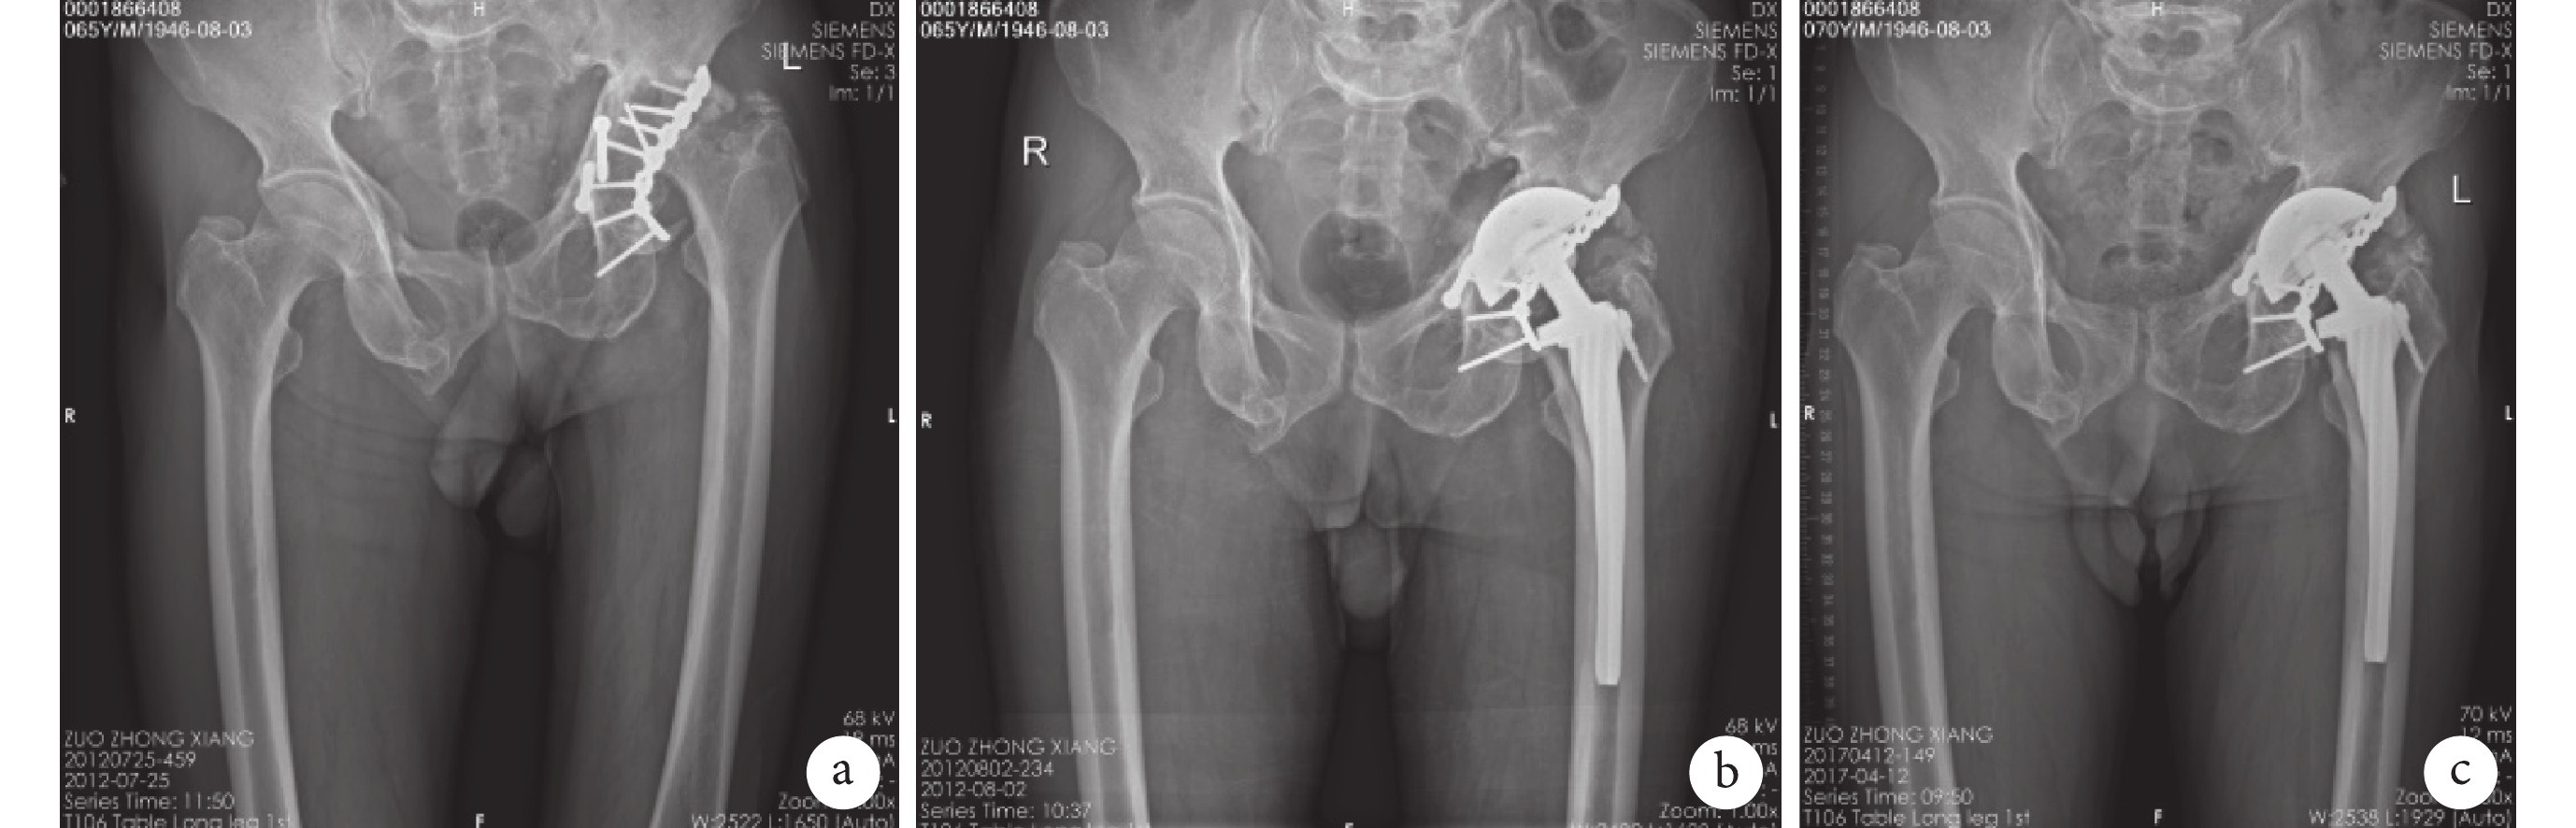

X 線片復查,隨訪期間 76 例(78 髖)股骨側出現透亮帶,位于 1 區 31 例(33 髖)、2 區 6 例(6 髖)、3 區 3 例(3 髖)、4 區 1 例(1 髖)、5 區 5 例(5 髖)、6 區 9 例(9 髖)、7 區 21 例(21 髖),無明顯硬化帶。術后 1 年,按照 Engh 等提出的方法評價假體穩定性,骨長入性穩定 364 髖、纖維長入性穩定 15 髖、假體不穩定 5 髖。對出現明顯透亮帶的 76 例(78 髖)進行應力遮擋分度,其中 1 度 45 髖、2 度 20 髖、3 度 9 髖、4 度 4 髖。末次隨訪,25 例(25 髖)發生股骨柄假體下沉,23 例為單髖置換患者,2 例為雙髖置換患者,但均為一側股骨柄假體下沉;雙下肢不等長 2~22 mm,平均 6.9 mm;16 例不等長≤5 mm、4 例 5 ~10 mm、5 例>10 mm。見圖 1、2。

a. 術前;b. 術后 1 d;c. 術后 5 年

Figure2. Anteroposterior X-ray films of a 66-year-old male patient underwent THA for avascular necrosis of the femoral head after 4 years of acetabular fracture internal fixationa. Before operation; b. At 1 day after operation; c. At 5 years after operation